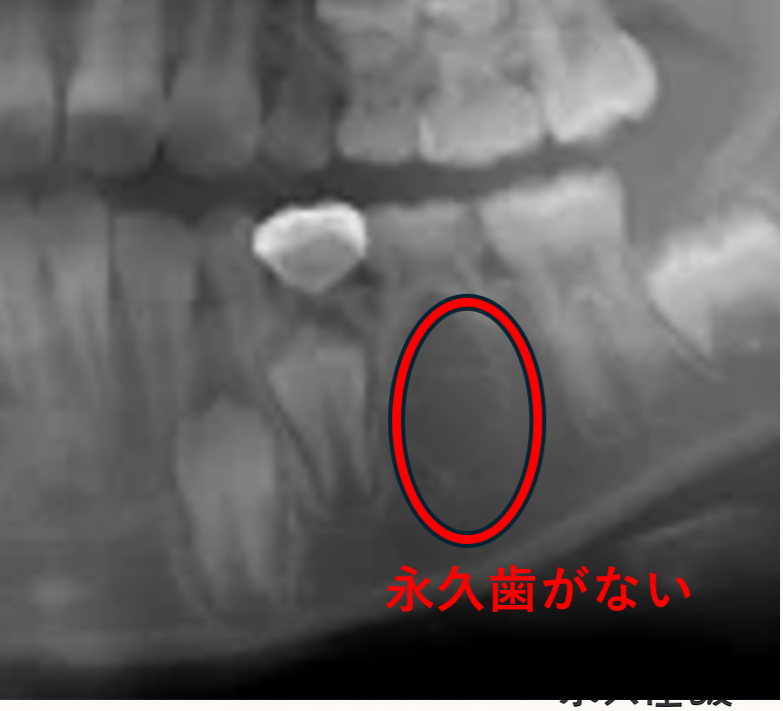

「歯の本数が足りない」永久歯の先天欠如について

永久歯の「先天欠如(せんてんけつじょ)」とは、生まれつき一部の永久歯の“種”が存在しない状態をいいます。

乳歯はすべて生えてくることが多いため、子どものうちは気づかれないことがほとんどです。

多くの場合、虫歯などを確認するために撮ったレントゲンで、結果的に先天欠如が見つかります。

特別な検査ではなく、日常的なチェックの中で偶然分かるケースが多いのです。

永久歯がなかなか生えてこない時期が続く場合は、まずレントゲンで歯の本数を確認しておくと安心です。